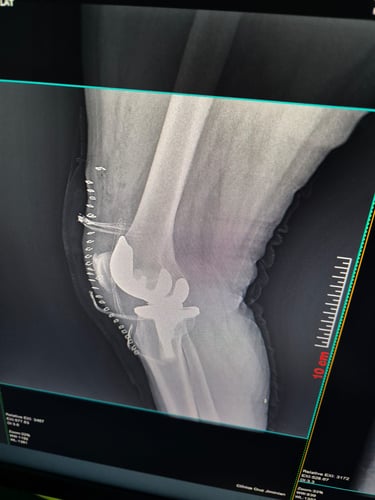

Cirugía de rodilla

Lesiones de meniscos y ligamentos (como LCA en rodilla)

Gallery

Provide a short description of the gallery, highlighting key things.